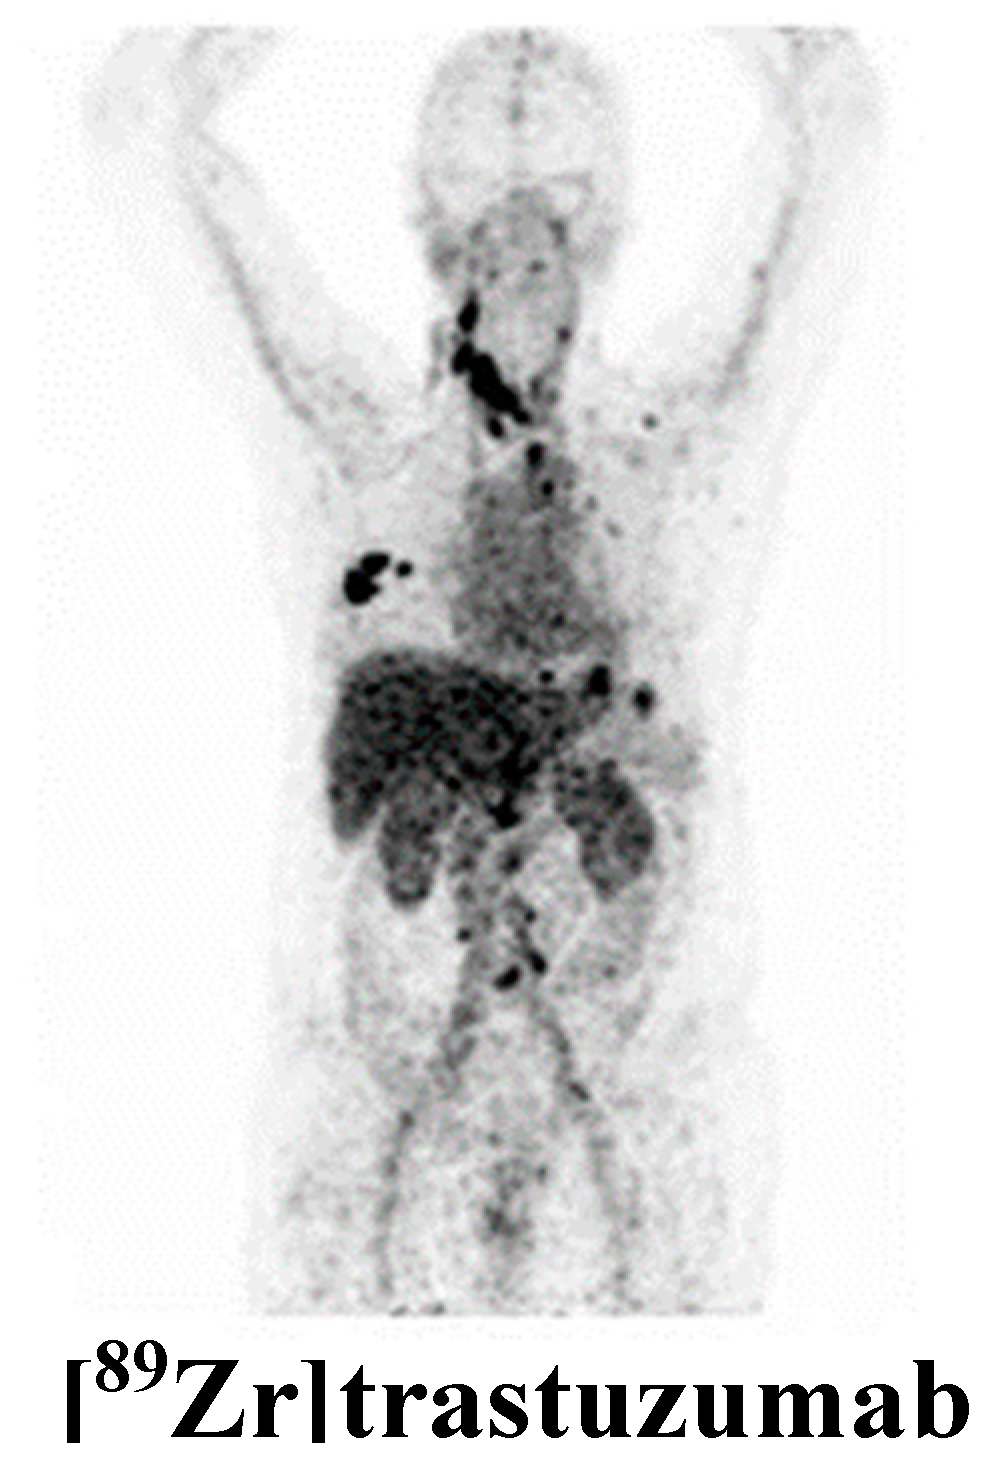

- Dijkers, E.C.; Oude Munnink, T.H.; Kosterink, J.G.; Brouwers, A.H.; Jager, P.L.; de Jong, J.R.; van Dongen, G.A.; Schröder, C.P.; Lub-de Hooge, M.N.; de Vries, E.G. Biodistribution of 89Zr-trastuzumab and PET imaging of HER2-positive lesions in patients with metastatic breast cancer. Clin. Pharmacol. Ther. 2010, 87, 586–592. [Google Scholar] [CrossRef]

- Gebhart, G.; Lamberts, L.E.; Wimana, Z.; Garcia, C.; Emonts, P.; Ameye, L.; Stroobants, S.; Huizing, M.; Aftimos, P.; Tol, J.; et al. Molecular imaging as a tool to investigate heterogeneity of advanced HER2-positive breast cancer and to predict patient outcome under trastuzumab emtansine (T-DM1): The ZEPHIR trial. Ann. Oncol. 2016, 27, 619–624. [Google Scholar] [CrossRef]

- Dehdashti, F.; Wu, N.; Bose, R.; Naughton, M.J.; Ma, C.X.; Marquez-Nostra, B.V.; Diebolder, P.; Mpoy, C.; Rogers, B.E.; Lapi, S.E.; et al. Evaluation of [89Zr]trastuzumab-PET/CT in differentiating HER2-positive from HER2-negative breast cancer. Breast Cancer Res. Treat. 2018, 169, 523–530. [Google Scholar] [CrossRef]